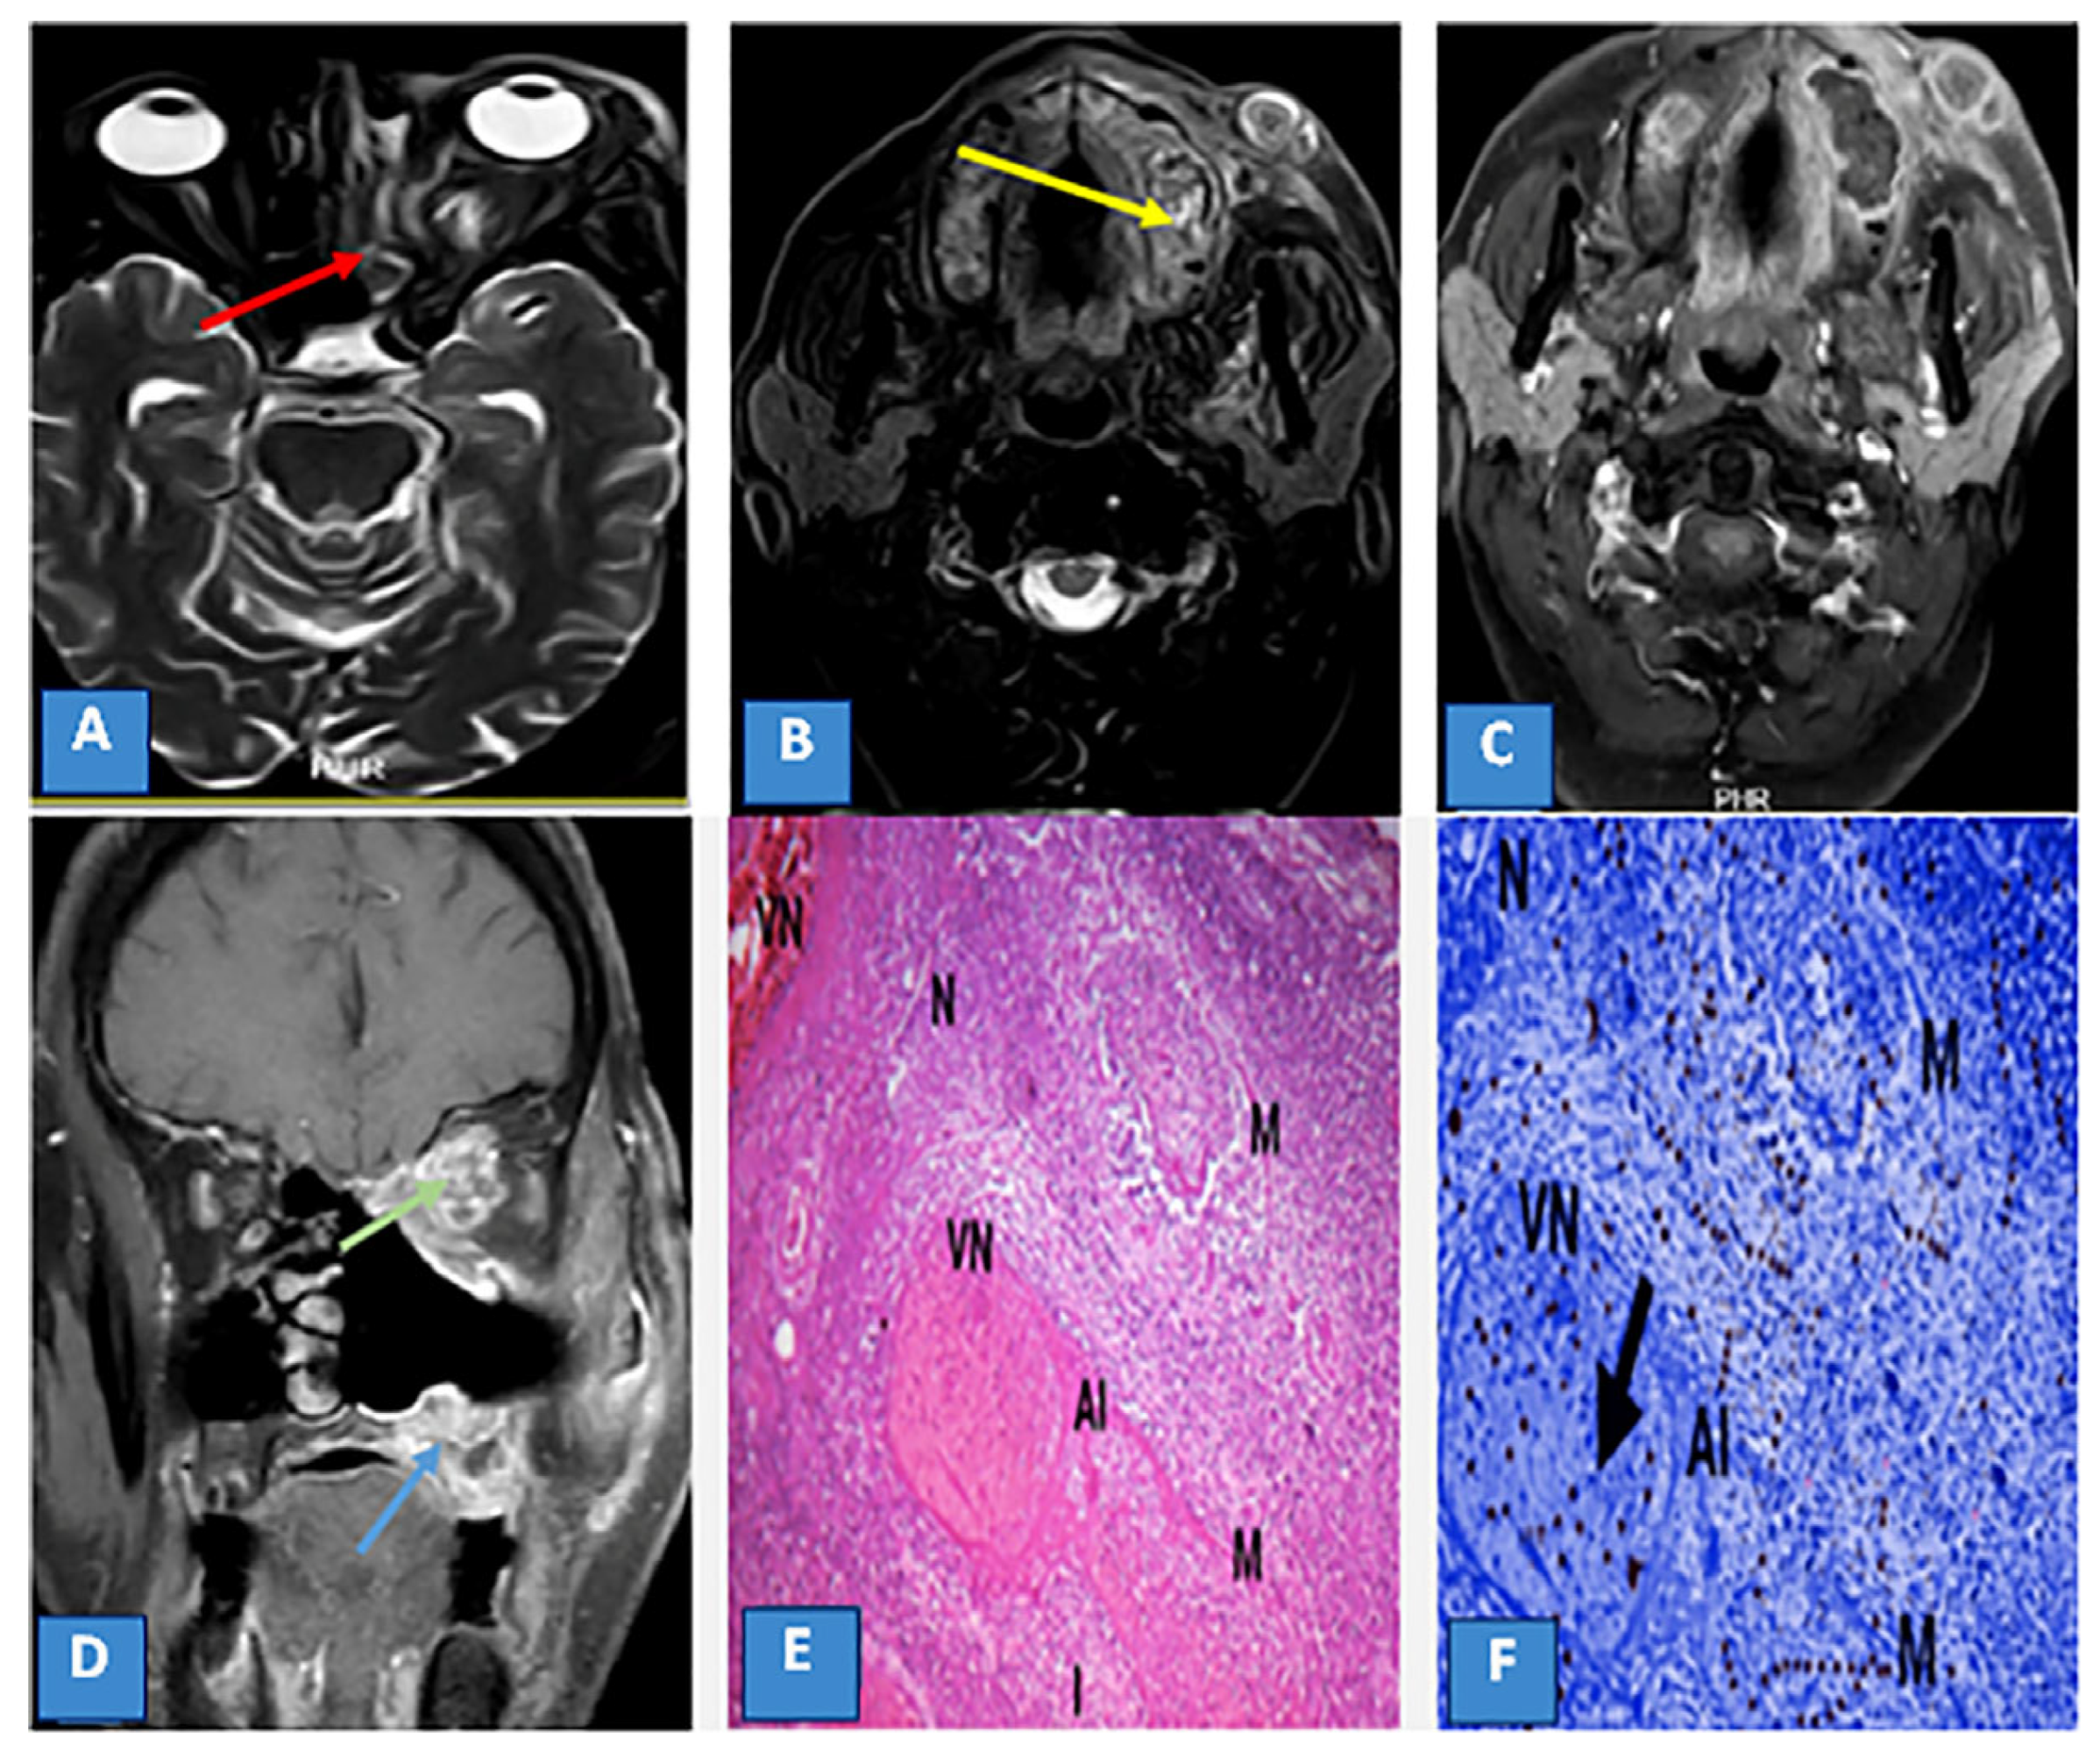

3.3. MRI Findings and Signal Characteristics

3.4. Extrasinus Extension

3.5. Histopathological Findings